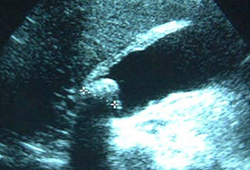

Colecistite aguda

Ultrassonografia de colecistite aguda e presença de cálculos biliares

Do acervo do Dr Charles Bellows; usado com permissão